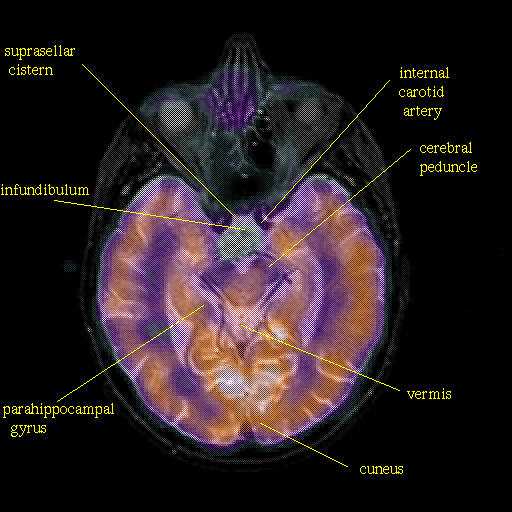

overlay: Slice 22

Slice 22

Pointers

Labeled